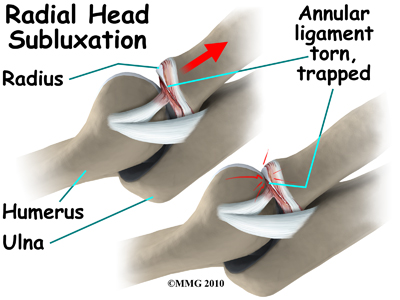

In young children, the annular ligament of the radial head is thin and weak. A sudden pull on the forearm can tear this soft tissue structure. The radial head is pulled down through the tear. The annular ligament slips into the radiohumeral joint and becomes trapped between the two joint surfaces when the arm is let go. This is a radial head subluxation. When the annular ligament is pinched it causes pain.

Reduction of the joint means that the joint is put back into normal alignment. Closed reduction refers to the fact that the subluxation of the annular ligament and radial head are put back in place without surgery. Generally this procedure is done in a clinic or hospital setting.

The technique of reduction is relatively simple. Once your child is calm and trust is established, the elbow is gently taken through a full range of motion from completely extended to fully flexed. While flexed the forearm is maximally supinated. In some cases, a small pop is felt or heard. This can indicate that the radial head and annular ligament have returned to their normal position. After relocation your child is encouraged to use the arm. In many cases, within minutes your child will be using the arm normally. If the child needs to feel more secure, a light splint can be used for a day or two.